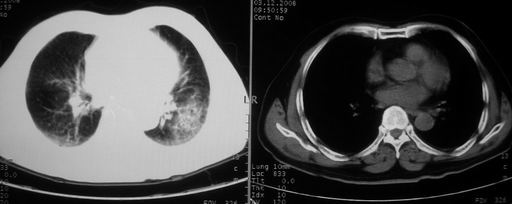

男,78岁,咳嗽、咳痰、发热入院,抗炎治疗一周后已退热,咳血似痰。

10月9日片: